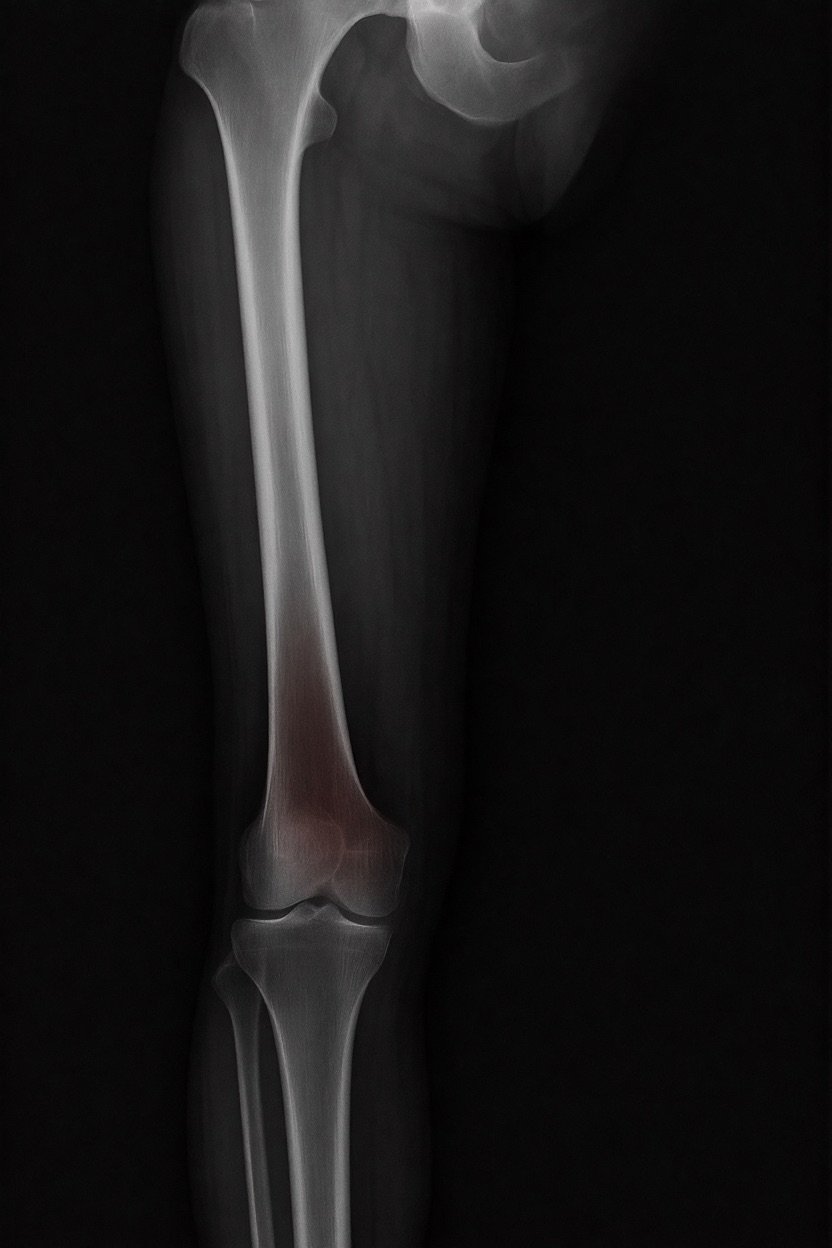

アートや写真の編集用に設計されたFlux Kontextのようなモデルを、医療画像、たとえば「単純な」骨折の赤色マーキングに使用できるか?

即答:面白い結果を出すが、過剰に反応し、医療ツールとしては信頼性に欠ける。これはアイデアを試すためのプロトタイプに過ぎない。

テスト結果:

- 偽陽性 ≈ 24%

- 骨折検出 ≈ 20%

感度モード(検出を優先、ノイズ多め)

- Euler、15ステップ、Karras

- Denoise:1.0

結果:

- 偽陽性 ≈ 80%

- 骨折検出 ≈ 86%

さらに攻撃的な設定(例:rk beta57、Denoise 1.0)では、**偽陽性100%、検出100%**という馬鹿げた結果に:すべてを赤で塗りつぶし、健常部もほぼすべて骨折と誤認する。未経験の目には区別がつかない。

Civitai用に作成した、100% AI生成の合成ミニデータセット(健康なX線10枚、骨折のあるX線10枚)でテスト:

- 健康な骨での偽陽性:100%

- 骨折検出:≈ 45%